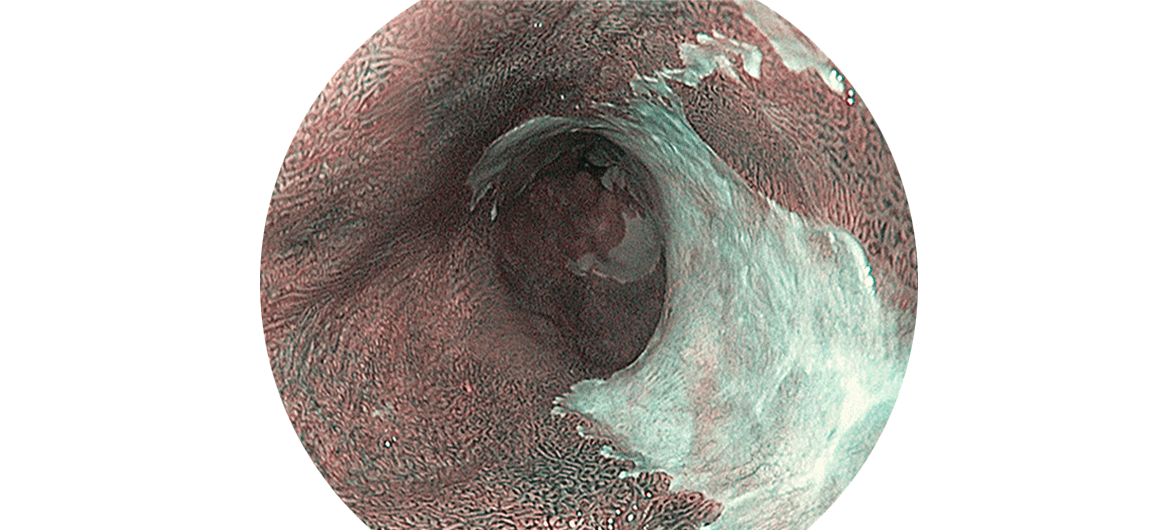

Barrett-Ösophagus

Der sogenannte Barrett-Ösophagus betrifft die Schleimhaut der Speiseröhre. Die Ursache ist eine Refluxerkrankung: Es fliesst Magensäure zurück in die Speiseröhre, weil der Schliessmuskel erschlafft oder zu schwach ist. Sofern dies über einen längeren Zeitraum hinweg geschieht, verändert sich mitunter das Gewebe im unteren Bereich der Speiseröhre.

Eine chronische Entzündung kann Verengungen im unteren Teil der Speiseröhre mit einhergehenden Schluckbeschwerden auslösen. Oft können die Verengungen endoskopisch behandelt werden. Des Weiteren kann die chronische Exposition mit Säure (oder auch nicht-saurem Inhalt) zu einer Umwandlung der Schleimhaut in der Speiseröhre führen. Diese „umgewandelte“ Schleimhaut nennt man Barrett-Schleimhaut (benannt nach dem britischen Chirurgen Norman Barrett, 1903 -1979). Drei bis fünfzehn Prozent der Patienten mit einer Refluxerkrankung entwickeln einen sogenannten Barrett-Ösophagus (Speiseröhre mit Barrett-Schleimhaut). Dieser kann zu einer bestimmten Krebsart der Speiseröhre führen, dem sogenannten Adeno-Karzinom.

Wichtig ist, dass die Schleimhaut durch einen erfahrenen Spezialisten und mit Endoskopen mit hoher Bildqualität beurteilt wird. Unregelmässigkeiten der Schleimhaut mit möglichen Krebsformen im Frühstadium müssen zuerst endoskopisch entfernt werden (endoskopische Mukosaresektion, EMR).